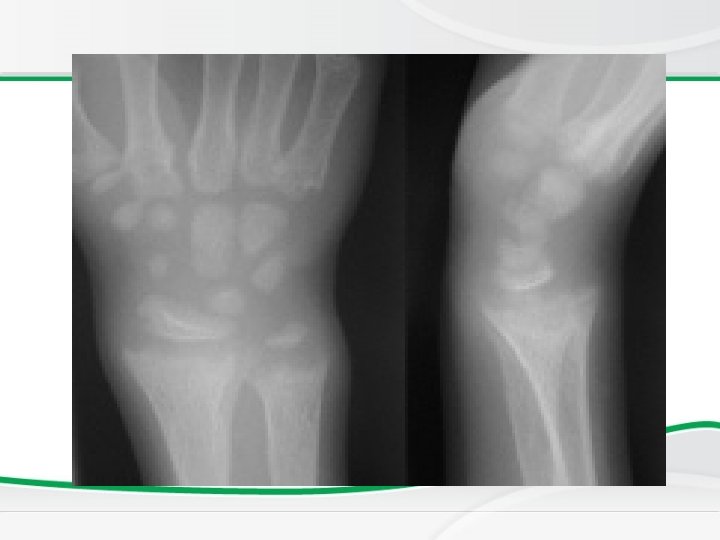

Investigations • BASIC INVESTIGATIONS TO CONFIRM RICKETS • • Low or normal serum Ca Low phosphorus (very early on in the disease may be normal) High alkaline phosphatase X rays of ends of long bones at knees or wrists – Shows Widening, fraying, cupping of the distal ends of shaft. • Vit D level low • Parathyroid hormone high is secondary due to hypocalcemia

Newborn Screening Rickets • Radiology changes

Genu valgus Wrist cupping Tri radiate pelvis Looser’s zones Wrist widening Wide metaphysis

• Full term 1 year old boy who presented with afebrile tonic clonic convulsions. He has no chronic illnesses or medication. On examination he has no apparent dysmorphic features and his vital signs were normal. a. Describe an abnormality. b. List two important investigations to confirm your diagnosis. c. What is the most likely diagnosis?

• Full term 1 year old boy who presented with afebrile tonic clonic convulsions. He has no chronic illnesses or medication. On examination he has no apparent dysmorphic features and his vital signs were normal. a. Describe an abnormality. b. List two other important investigations to confirm your diagnosis. Answer: a. Bowing of legs b. 1. Serum calcium level, serum alkaline phosphatase, 25 Vitamin D level, hand x-ray 2. Possible diagnosis is nutritional Vitamin D deficiency.